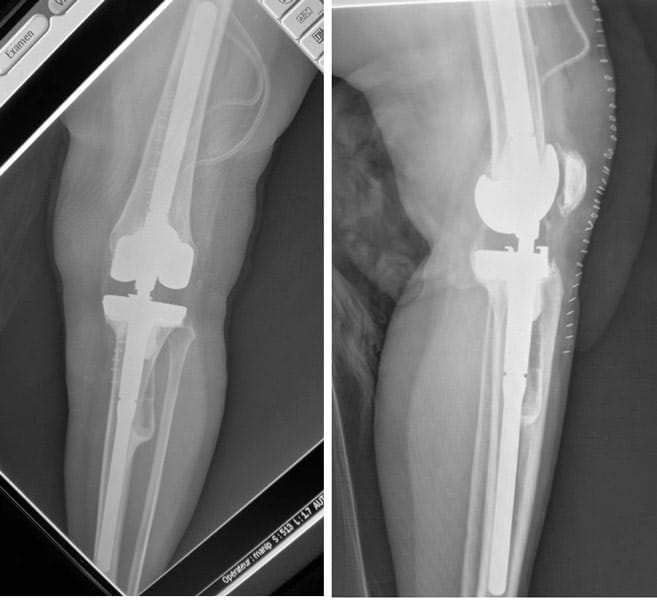

Homme 60 ans, Fracture complexe des 2 plateaux tibiaux opérée par plaques il y a 3 ans. Non consolidation osseuse.

Douleur, raideur.

Reprise par prothèse totale du genou postéro-stabilisée avec tige de reconstruction tibiale et reconstruction de l’appareil extenseur.